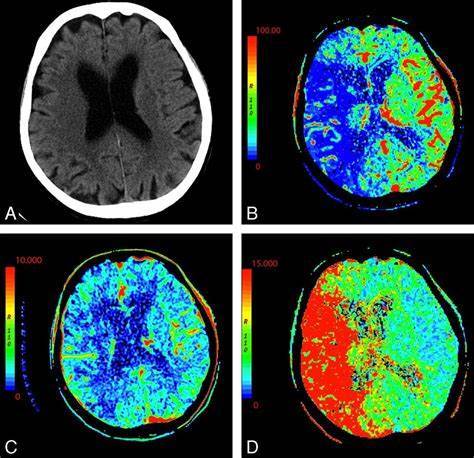

What imaging is done to distinguish the cause of stroke? (2)

CT

MRI

What is a Watershed Infarct?

Watershed cerebral infarctions (WI) , also known as border zone infarcts occur at the border between cerebral vascular territories where the tissue is furthest from arterial supply and thus most vulnerable to reductions in perfusion.